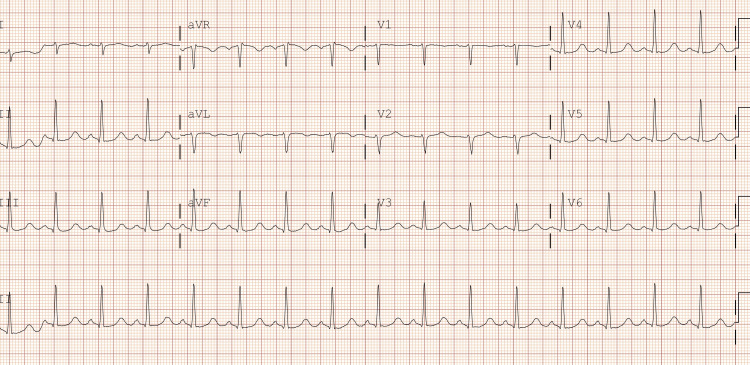

The patient was a 31-year-old female who arrived at the emergency department after being found unresponsive following an episode where she and a friend lost consciousness after using an unknown substance. The family denies any known hereditary diseases. Upon arrival, she required immediate intubation and cardiopulmonary resuscitation (CPR). Her initial ECG findings after the return of spontaneous circulation were consistent with bidirectional ventricular tachycardia, right axis deviation, terminal R wave, elongated QT interval, and a wide QRS complex. Resuscitative efforts included CPR, epinephrine administration, IV calcium gluconate, IV magnesium sulfate, and fluid resuscitation with lactated ringers and vasopressors. Laboratory findings revealed severe acidosis, leukocytosis, elevated ammonia, lactate, glucose, and abnormal liver enzyme levels, along with a positive urine drug screen for benzodiazepines, THC, cocaine, and fentanyl. Following successful resuscitation, the patient’s physical examination findings included fixed and dilated pupils, irregular rhythm with diminished carotid pulses, respiratory distress, and unresponsiveness. A subsequent ECG performed in the emergency room showed resolution of the ventricular tachycardia but revealed a prolonged QTc interval of 521 ms and right axis deviation (Figure 1). CT imaging revealed cerebral edema, and the patient was transferred to the ICU for further management, including intravenous fluid resuscitation, antibiotic therapy, sedation, and vasopressor support (Figure 2).